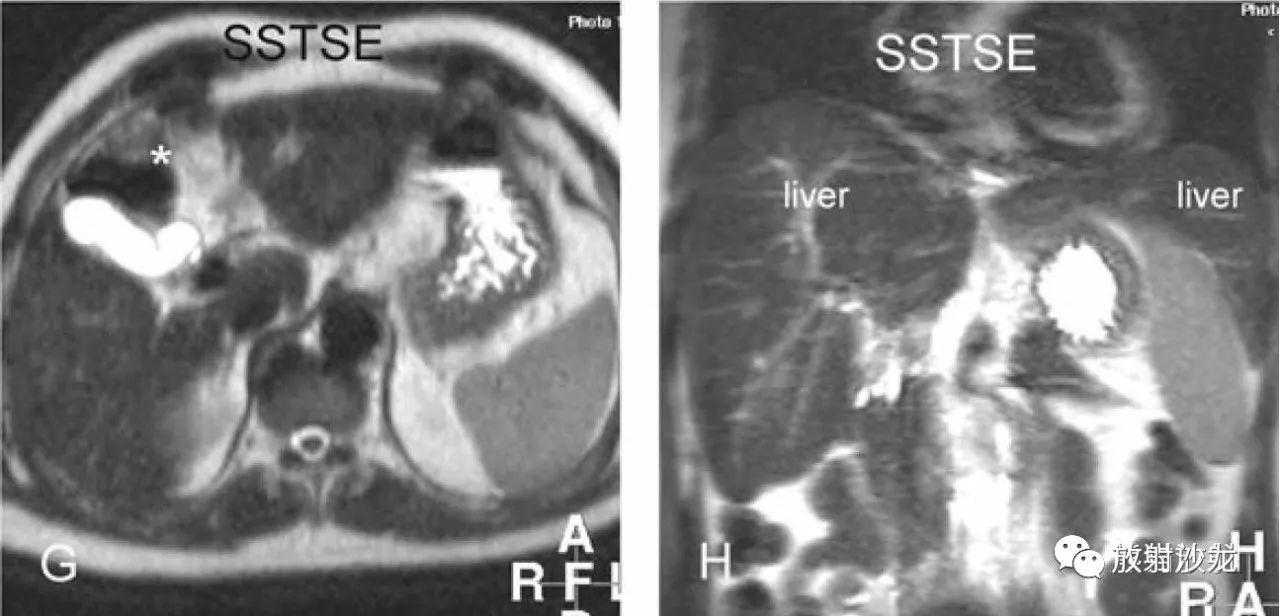

肝硬化,融合性肝硬化,MRI表现:

A~D:影像表现同上方所述。

E:DWI可显示更多的脾内GamnaGandy小体(铁沉积);

F:反相位,肝内可见多发的再生结节;

G:T2WI,肝轮廓不规则;

H:冠状T2WI,肝右叶萎缩,可见胆囊结石。

肝硬化,组织病理学(其他患者):